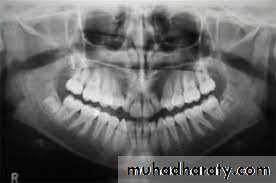

3. Radiography method

Types of X-ray radiograph images:• Periapical X-ray radiograph.

• Bitewing X-ray radiograph.

• Panoramic X-ray radiograph.

4. Trans illumination (Fiberoptic light)